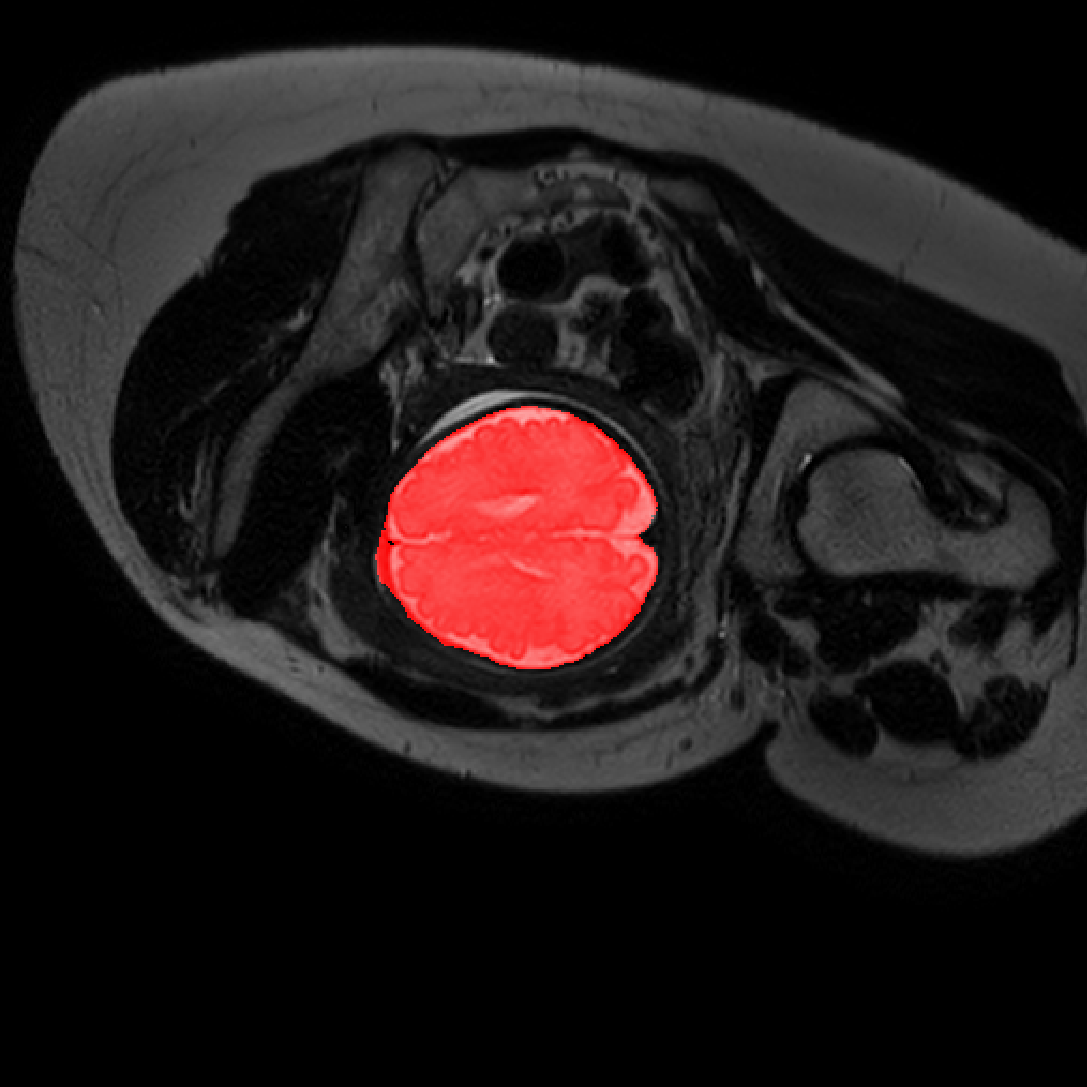

Table 1 lists average of quantitative evaluation results of these experiments and Figure 2 shows results obtained from each image. Figure 3 shows examples of the obtained segmentations.

Figure 3: Example of ICV segmentations in images acquired in axial (left), coronal (middle) and sagittal (right) planes. Top row: A slice from T2-weigted image; Second row: Automatic segmentations obtained using 7 training images from the representative imaging planes; Third row: Automatic segmentations obtained using all 21 training images from all 3 image orientations; Bottom row: Manual segmentation.